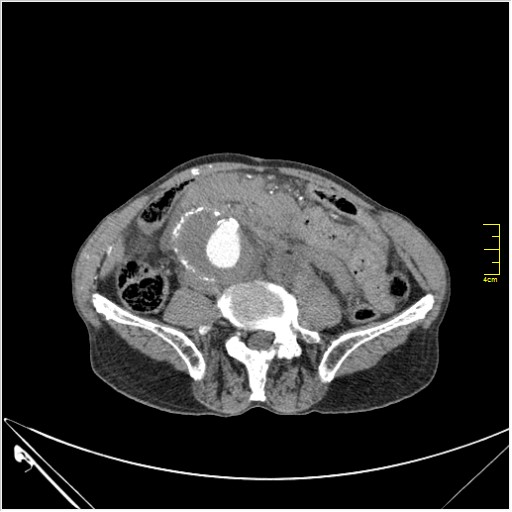

Пациент Т. 64 года, обратился на КТ брюшной полости амбулаторно (!), по направлению семейного врача с диагнозом abdominal mass, буквально: образование брюшной полости.

Huge abdominal aorta aneurism. Simple renal cortical cysts (Bosniak type 1).